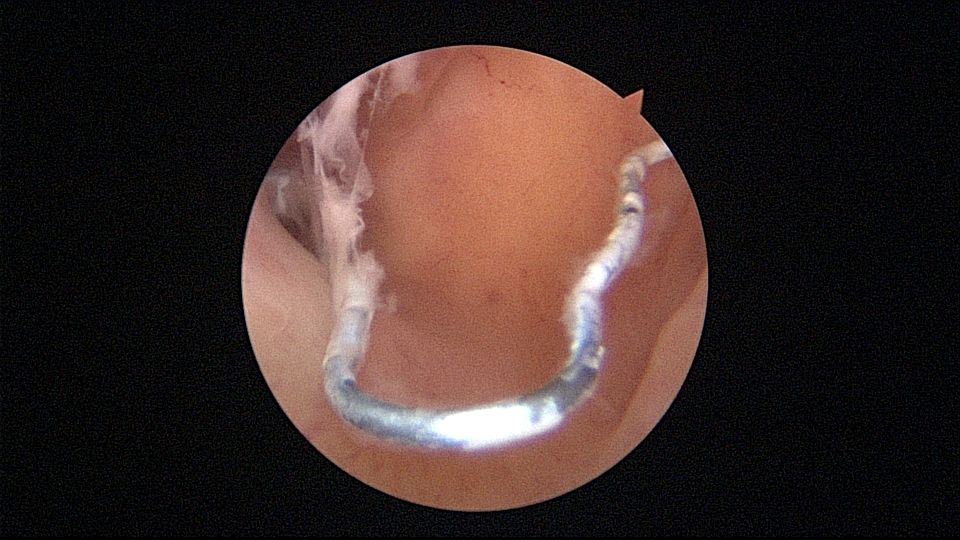

很有意思的一次取环经历:患者33岁,G2P1,剖宫产1次。安环7年,月经淋漓不尽3个月,2家医院取环失败,两次取环时间相隔24天,第二次取环失败后第二天到我院行宫腔镜取环。子宫后倾后屈位,剖宫产切口憩室处组织杂乱,爱母环位置正常,感觉是个比较简单的取环,取环钩探寻节育环,顺利取出。用刮匙准备诊刮,刮匙很容易进入,感觉很深,达13cm,但前面宫腔镜检查没有异常,以为是B超测量子宫有误,或者剖宫产粘连把子宫拉上去了,没有往子宫穿孔方面想,刮匙试探几次均是相同结果,试着刮了几下,没有内膜组织,再次置镜检查,结果镜子进入盆腔,看见网膜脂肪组织。宫颈内口闭塞,花了较多时间也进不去宫腔,穿孔处无出血,盆腔无积血,放弃诊刮。打电话给第二家取环医院的医生,得知前一天取环时感觉穿孔,放弃取环,介绍到我这里宫腔镜取环。分析整个过程,第一家医院在切口憩室处已穿孔,取环失败,穿孔处虽然愈合,却是一个薄弱环节,第二家医院和我们的宫腔镜均在该处进入盆腔,刮匙探查有底,是因为刮匙抵到了骶骨。